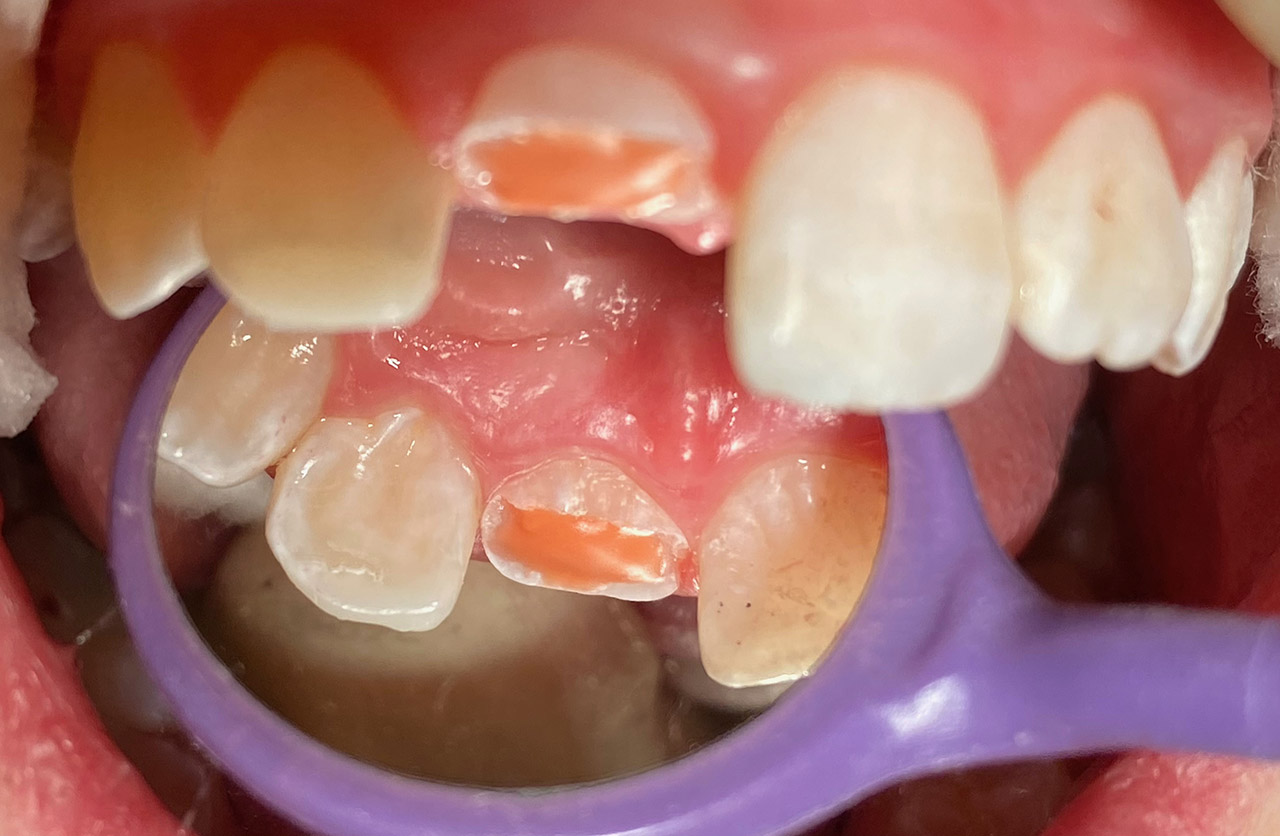

Internes und Externes Bleaching (Bleichen):

Nach Unfall mit E-Scooter unbefriedigendes Ergebnis der Erstversorgung (alio loco). Therapievorschlag: Stiftzähne?

Unsere minimalinvasive Therapie: Revision der Wurzelbehandlungen, danach internes und externes Bleaching, adhäsive Kunststoffüllungen in Schichttechnik. (Titel meiner Diplomarbeit 2003 “Die Vermeidung von Extraktion und Wurzelspitzenresektion durch zeitgemässe Endodontie in der Privatpraxis”)